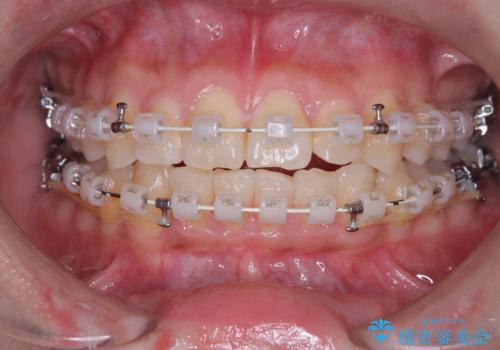

非抜歯で整える前歯の矯正

- 矯正装置

- 審美ワイヤー

- 患者様は、前歯の重なり(叢生)が気になるとのことでご来院されました。診断の結果、奥歯を後方に移動することで前歯にスペースを確保し、非抜歯で歯列を整える方針としました。治療には審美性の高いホワイトワイヤーを使用し、奥歯の遠心移動にはリンガルアーチを装着しました。治療期間は約2年を予定し、月に一度の調整を通じて歯の動きを細かく管理しました。

非抜歯矯正は、歯を抜かずに自然な歯列を作るため、歯列全体のバランスを考慮する必要があります。本症例では、リンガルアーチによる奥歯の遠心移動を用いましたが、初期段階で軽い違和感を覚える方もいらっしゃいます。そのため、装置装着後のケアや食生活について詳しく説明を行い、患者様にも協力いただきました。また、審美ワイヤーを使用することで、日常生活での見た目のストレスを軽減し、治療を快適に進めることができました。